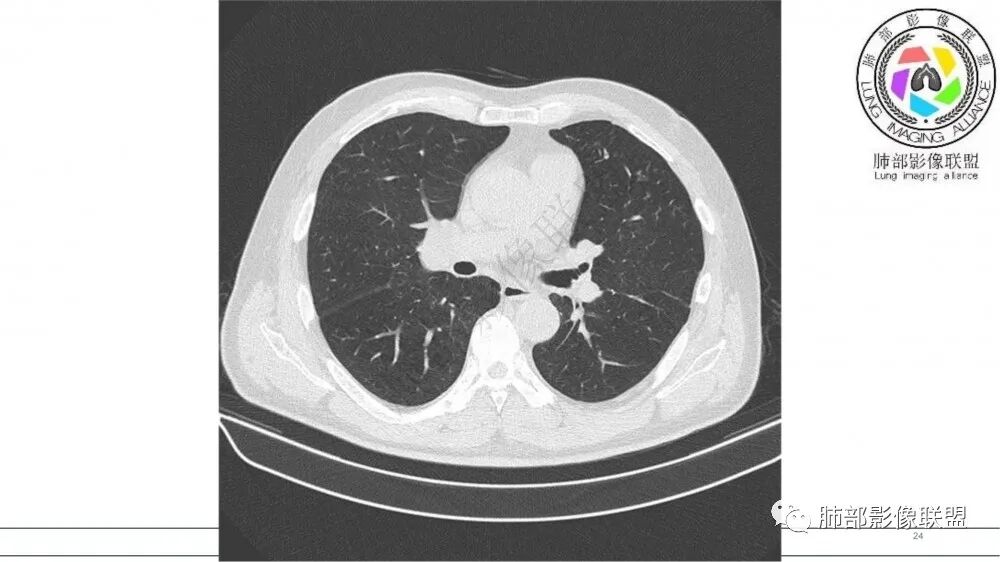

左肺上叶前段支气管内铸形生长软组织影,增强后均匀强化,远侧见斑片状磨玻璃影。考虑恶性病变,粘表?粘液腺?

老年男性,左肺上叶前段支气管内铸形阴影,增强后病灶不均匀强化,内部有坏死?远端可见斑片状阴影(阻塞性肺炎)。考虑恶性病变,老年人,鳞?类癌?粘表不能排除。

左肺上叶前段支气管杵状指样扩张,内见实性组织阻塞性,并强化明显,边缘饱满,周边多发小斑点影,小花小草征,老年男性,长期吸烟史,方向恶性,首选支气管内浸润鳞Ca可能性大。

老年男性,肺气肿,吸烟史,左肺上支气管腔内铸型高密度影,呈指套状,远端多发树芽,增强不均匀强化,考虑鳞癌,鉴别小细胞癌

老年男性,吸烟史,左肺上叶支气管铸形,变窄,轻度强化,周围阻塞性炎症,左肺门肿大淋巴结,考虑恶性,小细胞鉴别鳞癌

左肺上叶尖后段支气管近端截断,远端见高密度铸型,远侧见阻塞性改变,老年男性,吸烟史,考虑恶性,鳞癌。ABPA代排

指套征,扩张支气管内软组织强化,远侧肺野阻塞性炎,纵隔、左肺门肿大淋巴结;老年男性,吸烟,考虑鳞癌,鉴别小

指套征:是影像征象,胸部平片表现为手指状密度增高影,以肺门为中心呈放射状分布,CT显示扩张支气管内低密度黏液栓形成或实性病变,呈管状、树枝状或卵圆形密度增高影;支气管扩张伴近端梗阻时,扩张支气管内部黏液分泌物不能排出而形成。可以伴随远端空气潴留征、阻塞性炎症。

研究报道,中心型 SCLC 经 CT 扫描后通常支气管表现为鼠尾样狭窄,肺门或纵隔肿块明显,由于肿块沿管壁生长表现为顺延支气管形态的不规则形状。病灶相对特征性影像学表现比如鸭蹼状、腊肠状、葫芦状及葡萄状改变,可以出现血管包埋,很少有空洞、空泡,较少引发肺不张,阻塞性炎症成都较轻。与一般肺癌比较,恶性程度高,侵袭力强、病灶很小就容易远处转移!Herzberg 等[19]研究指出,20%以上 SCLC 倍增时间短,预后不良。